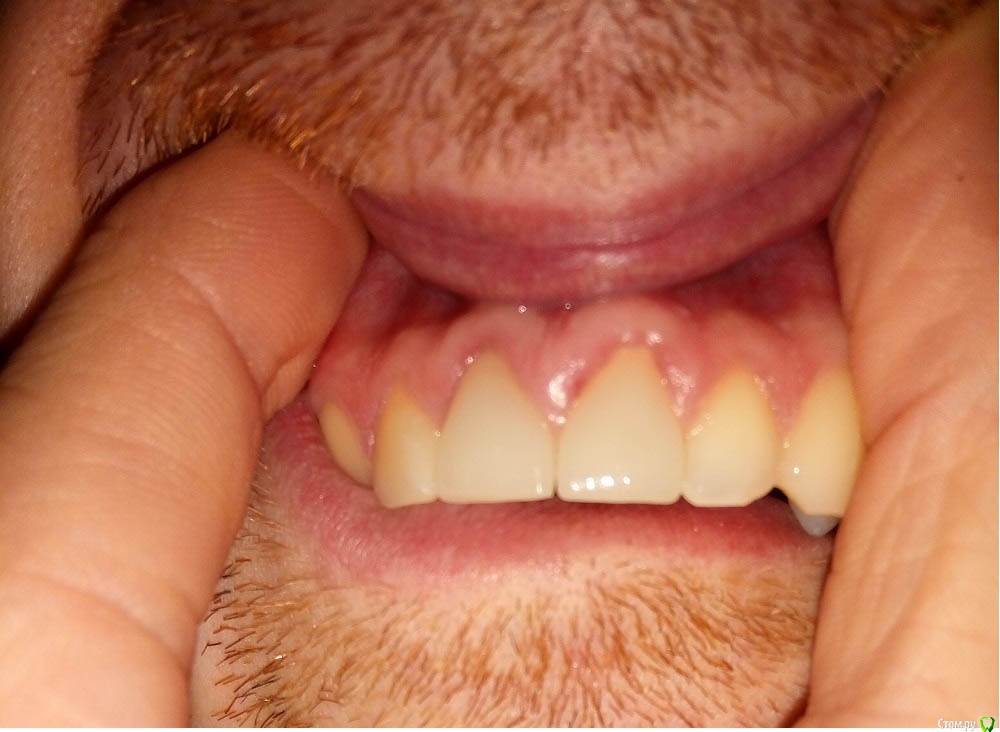

Opp80 Опубликовано 10 января, 2016 Автор Поделиться Опубликовано 10 января, 2016 (изменено) Чувствительность уменьшилась, но не прошла, далеко не прошла, пульсация периодическая и с отдачей в этот сосочек в периоды активного движения, т.е например поход в магазин, но не каждый раз (отметил на фото), у зуба есть небольшая подвижность так сказала другой врач на консультации, она сказала что возможно от того что врач постоянно лазил под десну, связки нарушаются, чтото типа того, но по симптоматике похоже на трещину, мой же врач на последней консультации, сказал может перфорация, и сказал делать ничего не будет больше, я же все мучаюсь, коронка поменяла свое положение появилась небольшая диастема за все время вмешательств.Прилагаю также понорамный снимок, и если кто глубоко заинтересуется КТ https://yadi.sk/d/TAjzSbIumYiyoP.S. когда попросил врача рентгены то он резко негативно высказался о том что я хочу спросить все на форуме, мол там не мастера, чему удивился чего бояться то, но снимки сказал даст, но они не понадобились я сделал КТ.Напомню, коронки стоят с 29 июля примерно, так и мучаюсь Изменено 10 января, 2016 пользователем Opp80 Ссылка на комментарий

Opp80 Опубликовано 10 января, 2016 Автор Поделиться Опубликовано 10 января, 2016 (изменено) Это снимок от 3 декабря (месяц назад) перед тем как врач будет до костной ткани все пробовать прочищать зондом, как понял так было, тут я немного боком сфотографировал диастема была уже но субъективно меньше Изменено 10 января, 2016 пользователем Opp80 Ссылка на комментарий

Opp80 Опубликовано 16 января, 2016 Автор Поделиться Опубликовано 16 января, 2016 (изменено) Уважаемые врачи посмотрите пожалуйста такие десна были до установок постоянок (фото 1,2) и после 3,4Это с коронками чтото нето? Изменено 16 января, 2016 пользователем Opp80 Ссылка на комментарий